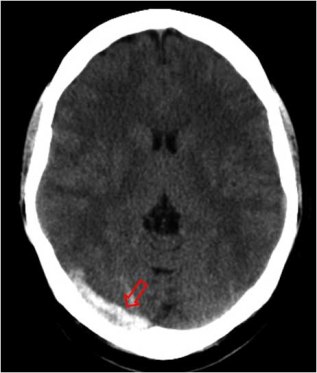

En el mismo paciente, un corte mas caudal muestra el trombo extendiéndose por el seno transverso derecho.